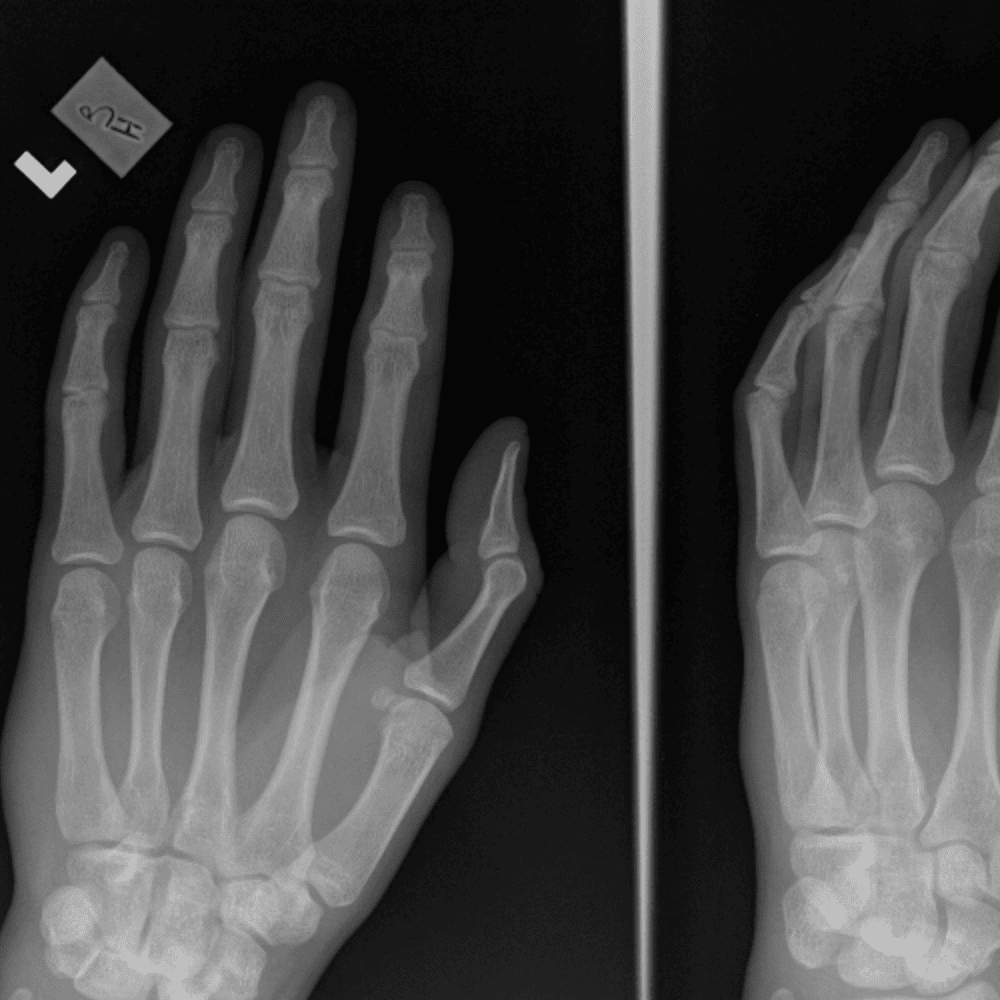

Simulates call by including subtle or difficult cases and some normals.

30 cases